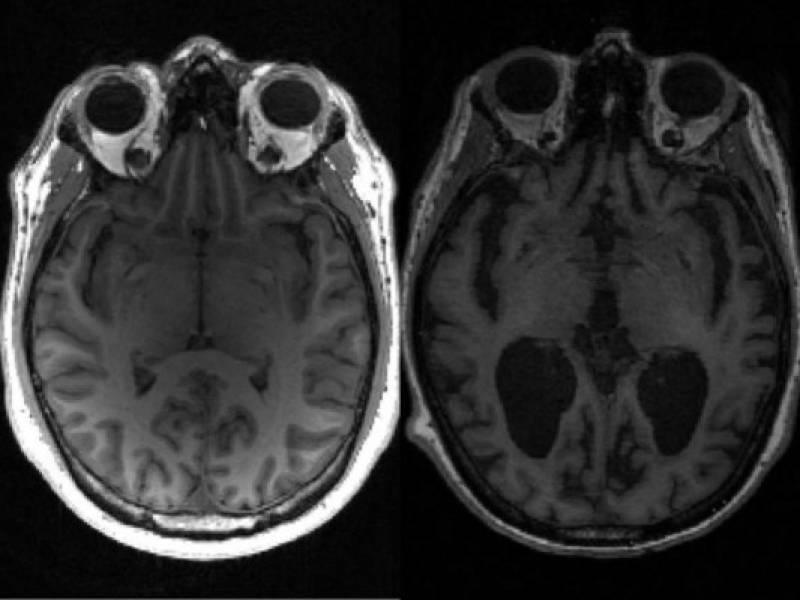

En la enfermedad de Alzheimer, dos proteínas clave -la tau y otra llamada beta-amiloide- se acumulan gradualmente de forma anormal en el cerebro, provocando la muerte de las células cerebrales y el encogimiento del cerebro.

Esto provoca la pérdida de memoria y una creciente incapacidad para realizar las tareas cotidianas.